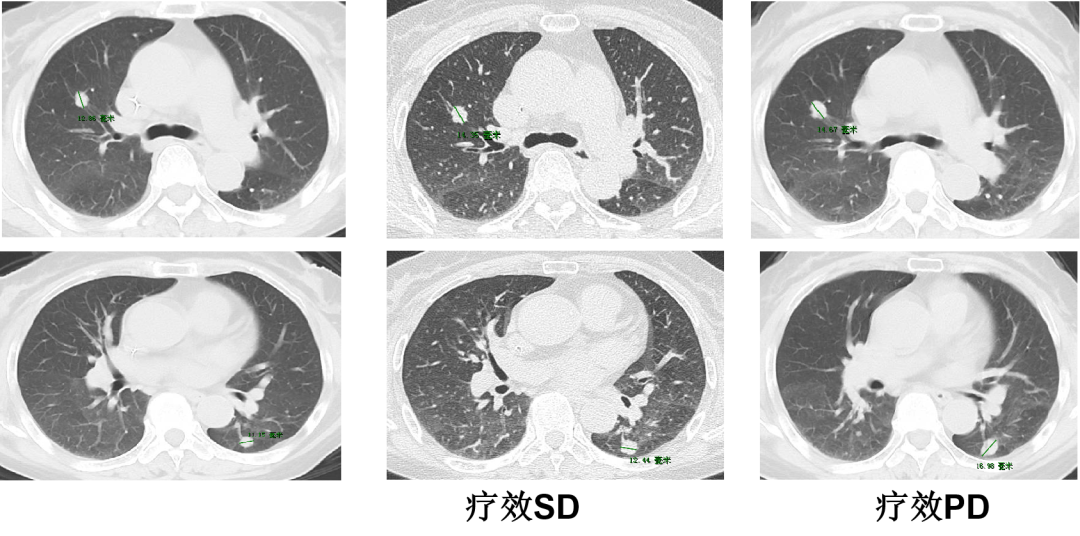

一 专家访谈 专家简介 于国华 教授 潍坊市人民医院 潍坊市肿瘤防治中心主任、潍坊市人民肿瘤医院院长、GCP机构副主任 潍坊市科技智库首席专家,省级重点学科负责人 中国临床肿瘤学会(CSCO)理事 山东省抗癌协会常务理事 潍坊市抗癌协会理事长 中国老年学学会舒缓治疗分会常务委员 中国老年学学会老年肿瘤专业委员会 中国老年学学会老年肿瘤专业委员会(CGOS)分子靶向分委会、肺癌分委会常务委员 山东省医学会肿瘤微创治疗分会副主任委员 山东省医学会姑息医学分会副主任委员 山东省肿瘤微创质量控制中心副主任委员 山东省医师协会肿瘤化疗医师分会副主任委员 山东省抗癌协会肿瘤化疗分会、肺癌分会、靶向治疗分会、心理治疗分会副主任委员 潍坊市医学会肿瘤化疗分会主任委员 潍坊市中西医结合学会肿瘤专业委员会主任委员 潍坊市肿瘤化疗专业质量控制中心主任 Q1 随着检查手段不断丰富,晚期结直肠癌的全程管理成为必然趋势。请您谈一谈我国在结直肠癌全程管理方面取得了哪些成果,未来应该朝着哪些方向努力? 我国在结直肠癌全程管理方面的进步成果,大概可以分为三个方面。 第一方面,随着医疗检测技术和诊疗理念的革新,我国早筛早治取得了良好进展。60~80年代我国检查技术相对落后,主要为粪便潜血试验展开有关肠道检查,而随着内镜技术的发展,肠镜检查逐渐普及,提高了结直肠癌早期患者的诊断率,推进了我国早诊早治的策略,使更多患者及早发现疾病并接受治疗。 第二方面,我国医疗制度具有优越性。随着我国全民医保的全面落实,“全民健康”理念的普及,就诊路径日益优化,更加快速便捷,使患者尽早获得诊断和治疗。 第三方面,国家癌症中心以及有关学协会的成立,推动了我国整体诊疗水平的不断提高。不仅为基层和各级医院搭建了良好的学习平台,推动了临床医生的再学习、再教育,也使得规范化诊疗、多学科协作(MDT)等优秀诊疗理念得以推广和实践。 第四方面,在内外科领域,药物治疗和手术治疗也是发展比较迅速。我国加速推进新药研发和医药服务创新,使更多药物尽快落地,惠及我国患者。相有关学协会积极组织形成了具有实践和指导意义的全程管理专家共识/指南,包括患者自身情况的评估、围手术期管理、治疗药物的选择、各线药物治疗方案、药物不良反应管理等。 关于结直肠癌全程管理未来的发展,需要以预防、规范化治疗和新药研发为抓手。 第一方面,预防是结直肠癌管理的第一步,未来有待在国家层面开展大规模的宣传教育,科普健康生活方式,令群众了解结直肠癌危险因素,从源头降低结直肠癌的患病风险。 第二方面,早筛早诊尽管已经取得显著成效,等仍需要深入基层,覆盖偏远贫困地区,使更多结直肠癌患者能够在早期发现,尽早干预,提升结直肠癌患者整体生存和预后。 第三方面,结直肠癌诊疗规范有待进一步提升,尤其需要在基层医疗单位加强规范化诊疗的理念。 第四方面,精准医学时代背景下,我们希望未来随着分子水平研究和精准医学研究的进展,在疗效监测和复发监测方面能使用更精准、更有价值的分子标志物动态监测。在手术前判断患者是否需要先做辅助化疗,在手术后判断是否需要进行复发监测,通过分子标志物可以更早地提示未来是否会复发,是否需要提前干预,如果复发,分子标志物可以再次作为监测指标指导治疗。 第五方面,我们还需加大研发力度,开发更多新机制、新靶点的药物,进一步提升晚期结直肠癌的疗效。 Q2 长期以来,化疗始终是肿瘤治疗领域的基石。其中,曲氟尿苷替匹嘧啶片(TAS-102)作为新型口服化疗药,问世以来不断为结直肠癌领域打开新的治疗格局,请您谈谈该药在中国的上市是基于怎样的研究成果? TAS-102在中国的获批是基于国际多中心 RECOURSE 研究和亚太TERRA研究的结果。RECOURSE研究是TAS-102的国际多中心Ⅲ期临床研究,显示TAS-102较安慰剂显著延长中位OS时间(7.1个月对比5.3个月)和中位PFS时间(2.0个月对比1.7个月),死亡风险和疾病进展风险分别降低32%和52%。此后,有众多中国临床专家参与的TERRA研究,证实了TAS-102在亚洲人群的安全性和有效性,TERRA研究重复出了RECOURCE研究的结果,TAS-102组患者的中位OS时间(7.8个月对比7.1个月)和PFS时间(2.0个月对比1.8个月)得到显著改善,死亡风险和疾病进展风险分别降低21%和57%。这两项关键研究成功改写了包括ESMO、NCCN、CSCO等中外权威指南的推荐。 而且,这两项研究中,TAS-102的不良反应均以血液学毒性为主,有症状的不良反应发生率低。鉴于其良好的安全性和耐受性,TAS-102与其他药物联合用于肠癌也在研究中进行了探索并取得了不错的结果。 Q3 晚期结直肠癌的发生通常预示着预后相对较差、患者生存期不长,但依然有治愈的可能,这关系到临床治疗用药方案的决策。今年上半年发布的CACA-RC指南推荐不适合强烈治疗患者应用TAS-102联合贝伐珠单抗,作为晚期不可切除结直肠癌姑息一线治疗方案。请您谈谈该推荐治疗对我国晚期不可切除结直肠癌的临床治疗产生了怎样的影响? 晚期转移性结直肠癌的标准化疗方案在指南中是以奥沙利铂或伊立替康为基础的FOLFOX和FOLFIRI方案,在此基础上,可以联合西妥昔单抗或贝伐珠单抗,但是,依旧有部分患者身体状况无法耐受加强化疗,少数患者因为高敏可能出现药物过敏,针对这一类患者,治疗方案的选择非常有限且预后情况并不理想。临床上往往推荐口服化疗药物+贝伐珠单抗方案。 2022年CACA-RC指南基于TASCO1研究的结果,推荐拒绝静脉化疗或不能耐受强烈治疗、易敏的晚期肠癌患者姑息一线选择TAS-102+贝伐珠单抗方案。TASCO1研究是一项旨在随机比较TAS-102+贝伐珠单抗和卡培他滨+贝伐珠单抗在一线治疗不可接受强烈治疗的不可切除转移性结直肠癌的Ⅱ期研究。研究结果显示:TAS-102组延长患者mPFS时间1.41个月(9.23个月对比7.82个月);延长患者mOS时间4.64个月(22.31个月对比17.67个月)。安全性分析也提示TAS-102+贝伐珠单抗治疗具有良好的耐受性,它最常发生的3/4级不良事件是中性粒细胞减少症。严重的发热性中性粒细胞减少症发生率约为4%。TAS-102+贝伐珠单抗方案因其高效、低毒的特点为不适合强烈治疗的转移性结直肠癌患者及老年患者带来了新的希望,其疗效与生存获益令人期待。 Q4 近年来,结直肠癌领域联合治疗的研究探索不断取得进步。请您谈谈,还有哪些研究进展为TAS-102联合贝伐珠单抗奠定一线治疗地位打下基础? 近年来,多项临床研究不断为TAS-102的临床可及性打下良好基础,DANISH研究将TAS-102与贝伐珠单抗联合用于转移性结直肠癌二线及以上治疗,发现联合组较TAS-102单药组疗效更好,中位PFS时间(4.6个月对比2.6个月)和OS时间(9.4个月对比6.7个月)显著延长,且联合组安全性可控,未出现非预期的不良反应。日本C-TASK-FORCE研究和欧洲DANISH研究均显示,对于PS为0~1分的转移性结直肠癌患者,TAS-102+贝伐珠单抗三线治疗实现了超过4.5个月的中位无进展生存期(PFS),超越了既往单药三线治疗的总体水平,且未显著增加不良事件(AEs)。TAS-102+贝伐珠单抗4周方案治疗转移性结直肠癌显示了良好的抗肿瘤活性。日本BiTS研究确证了双周方案可在不影响疗效的前提下,明显降低中性粒细胞减少症发生率。日本KSCC 1602研究和欧洲TASCO1研究都成功探索了FTD/TPI+贝伐珠单抗用于转移性结直肠癌一线治疗的疗效和安全性。 二 病例分享 专家简介 任海朋 主任 潍坊市人民医院 潍坊市人民医院肿瘤内科副主任,副主任医师 中国抗癌协会肿瘤微创治疗专业委员会委员 中国抗癌协会肿瘤消融治疗专业委员会委员 山东省健康管理协会消化道肿瘤防治分会副主任委员 山东省抗癌协会青年理事会常务理事 山东省医学会肝脏肿瘤多学科联合委员会委员 山东省抗癌协会消化道肿瘤分会委员 潍坊市医学会结直肠癌多学科联合专委会副主任委员 潍坊市医学会肿瘤微创治疗专业委员会副主任委员 潍坊市医师协会肿瘤化疗医师分会副主任委员 肖海凤 医师 潍坊市人民医院 潍坊市人民医院肿瘤内科主治医师,硕士 山东省抗癌协会化疗分会青年委员会委员 山东省疼痛医学会癌痛与姑息治疗专业委员会委员 山东省医学会科学普及分会肿瘤科普学组委员 山东省医学会精准医学分会消化道肿瘤学组委员 潍坊市医学会化疗专业委员会委员兼秘书 潍坊市抗癌协会乳腺癌专业委员会委员 潍坊市抗癌协会妇科肿瘤分会委员 潍坊市医学会第三届肛肠外科专业委员会青年学组委员 01 基本情况 基本情况:史xx,女,57岁,既往体健,无特殊病史,无家族史。 简要病史: 2020.1 患者出现大便带血,为暗红色,与大便相混,伴大便次数增多3~4次/天,大便不成形,伴肛门坠胀及里急后重感。 2020.4 就诊于潍坊市人民医院消化内科门诊,行肠镜示距肛门10cm环周隆起性病变,肠腔狭窄,镜身不能通过,考虑直肠癌,活检病理示腺癌(中分化)。 2020.4.16 就诊于我院肛肠外科一区,行胸腹盆部CT提示乙状结肠占位,考虑肿瘤,盆腔肿大淋巴结,双肺多发转移瘤。 诊断:直肠癌(cT3N+M1a,IVa期)。 2020.4.18 肺多发转移(CT) 2020.4.18 直肠原发灶(CT) 2020.5.12 基因检测 KRAS:Exon2、Exon3无突变;NRAS:Exon2、Exon3 无突变;BRAF:Exon15(V600E)无突变。UGT1A1*28:TA6/7,UGT1A1*6:G/G。MSS。 02 治疗经过 因直肠原发灶进镜困难,肠腔狭窄,发生肠梗阻风险较大,建议先行原发灶切除,后行全身抗肿瘤治疗。 2020.4.23 行直肠癌根治术(前切除术)+回肠预防性造口术+肠粘连松解术。 术后病理 一线治疗经过 2020.5.18至2021.1.31 行奥沙利铂甘露醇注射液225mg d1+卡培他滨1.5g bid d1-14方案化疗8周期。 不良反应:胃肠道反应不著,骨髓抑制最重2度。 疗效评价:5周期后疗效评价为PR,8周期后疗效评价为PD。 双肺转移灶(一线) 二线治疗经过 入住我科,ECOG 0分,身高159cm,体重65kg,体表面积1.64m2。 2021.3.9、2021.3.29、2021.4.12、2021.5.6、2021.5.25、2021.6.21、2021.7.9、2021.7.28、2021.8.15行西妥昔单抗800mg d1+伊立替康300mg d2+氟尿嘧啶650mg iv,4000mg civ 46h+左亚叶酸钙325mg d2化疗9周期。 不良反应:胃肠道反应不著,骨髓抑制2度。 疗效评价:缩小的SD。 双肺转移灶(二线) 三线治疗经过 2021.9至2022.5.6 口服呋喹替尼5mg qd d1-21 q28d治疗。 不良反应:高血压病1级,轻度肝功损伤。 疗效评价:2个月后疗效评价PR,7个月后肺内病灶增大,肝内出现新发病灶,疗效评价PD。 双肺转移灶(三线) 肝脏(新发病灶) 四线治疗经过 2022.5至今 开始应用贝伐珠单抗300mg d1联合TAS-102 55mg bid d1-5双周治疗。 不良反应:高血压2级,继发性甲状腺功能减退,白细胞减少I度,中性粒细胞减少2度,贫血1级。 疗效评价:PR。 03 病例小结 04 心得体会 TAS-102是一种新型口服细胞毒药物,是口服的氟尿嘧啶类药物,作用机制不同于氟尿嘧啶,可用于氟尿嘧啶耐药患者。 国际RECORSE和亚太TERRA研究证实,TAS-102在mCRC治疗中具有一致的疗效和安全性:1.显著延长mCRC患者生存期,降低死亡和疾病进展风险,尤其对于≥65岁患者获益更显著;2.显著延缓体能下降,为持续治疗提供体能储备;3.主要不良事件为血液学毒性。 双周TAS-102联合贝伐单抗不仅不降低疗效,而且明显降低中性粒细胞减少症发生率。 *本文仅代表专家观点,并经专家审校。